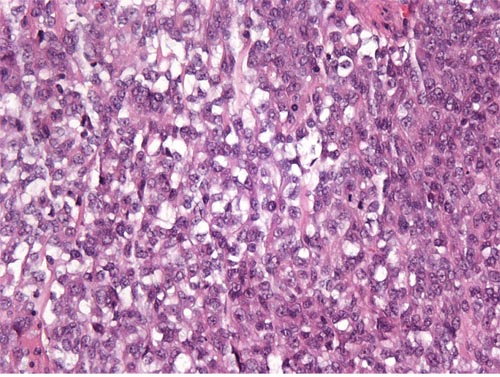

On microscopic examination, 9 cases showed features of low-grade ESS. The tumors were typically composed of sheets of small, closely pack cells resembling the stromal cells of the proliferative endometrium, with scant cytoplasm and round to oval nuclei (Figure 1). Sex cord-like differentiation was observed focally in 2 cases. Five cases showed features of high-grade ESS. The tumors were characterized by a monomorphic proliferation of round cells, which were larger than those of low-grade ESS with increased cytoplasm and high-grade cytologic atypia (Figure 2). Three of the five cases of high-grade ESS had a component of low-grade ESS.

Figure 2: High-grade ESS. The tumor is composed of atypical round cells. (original magnification × 400, hematoxylin-eosin stain).